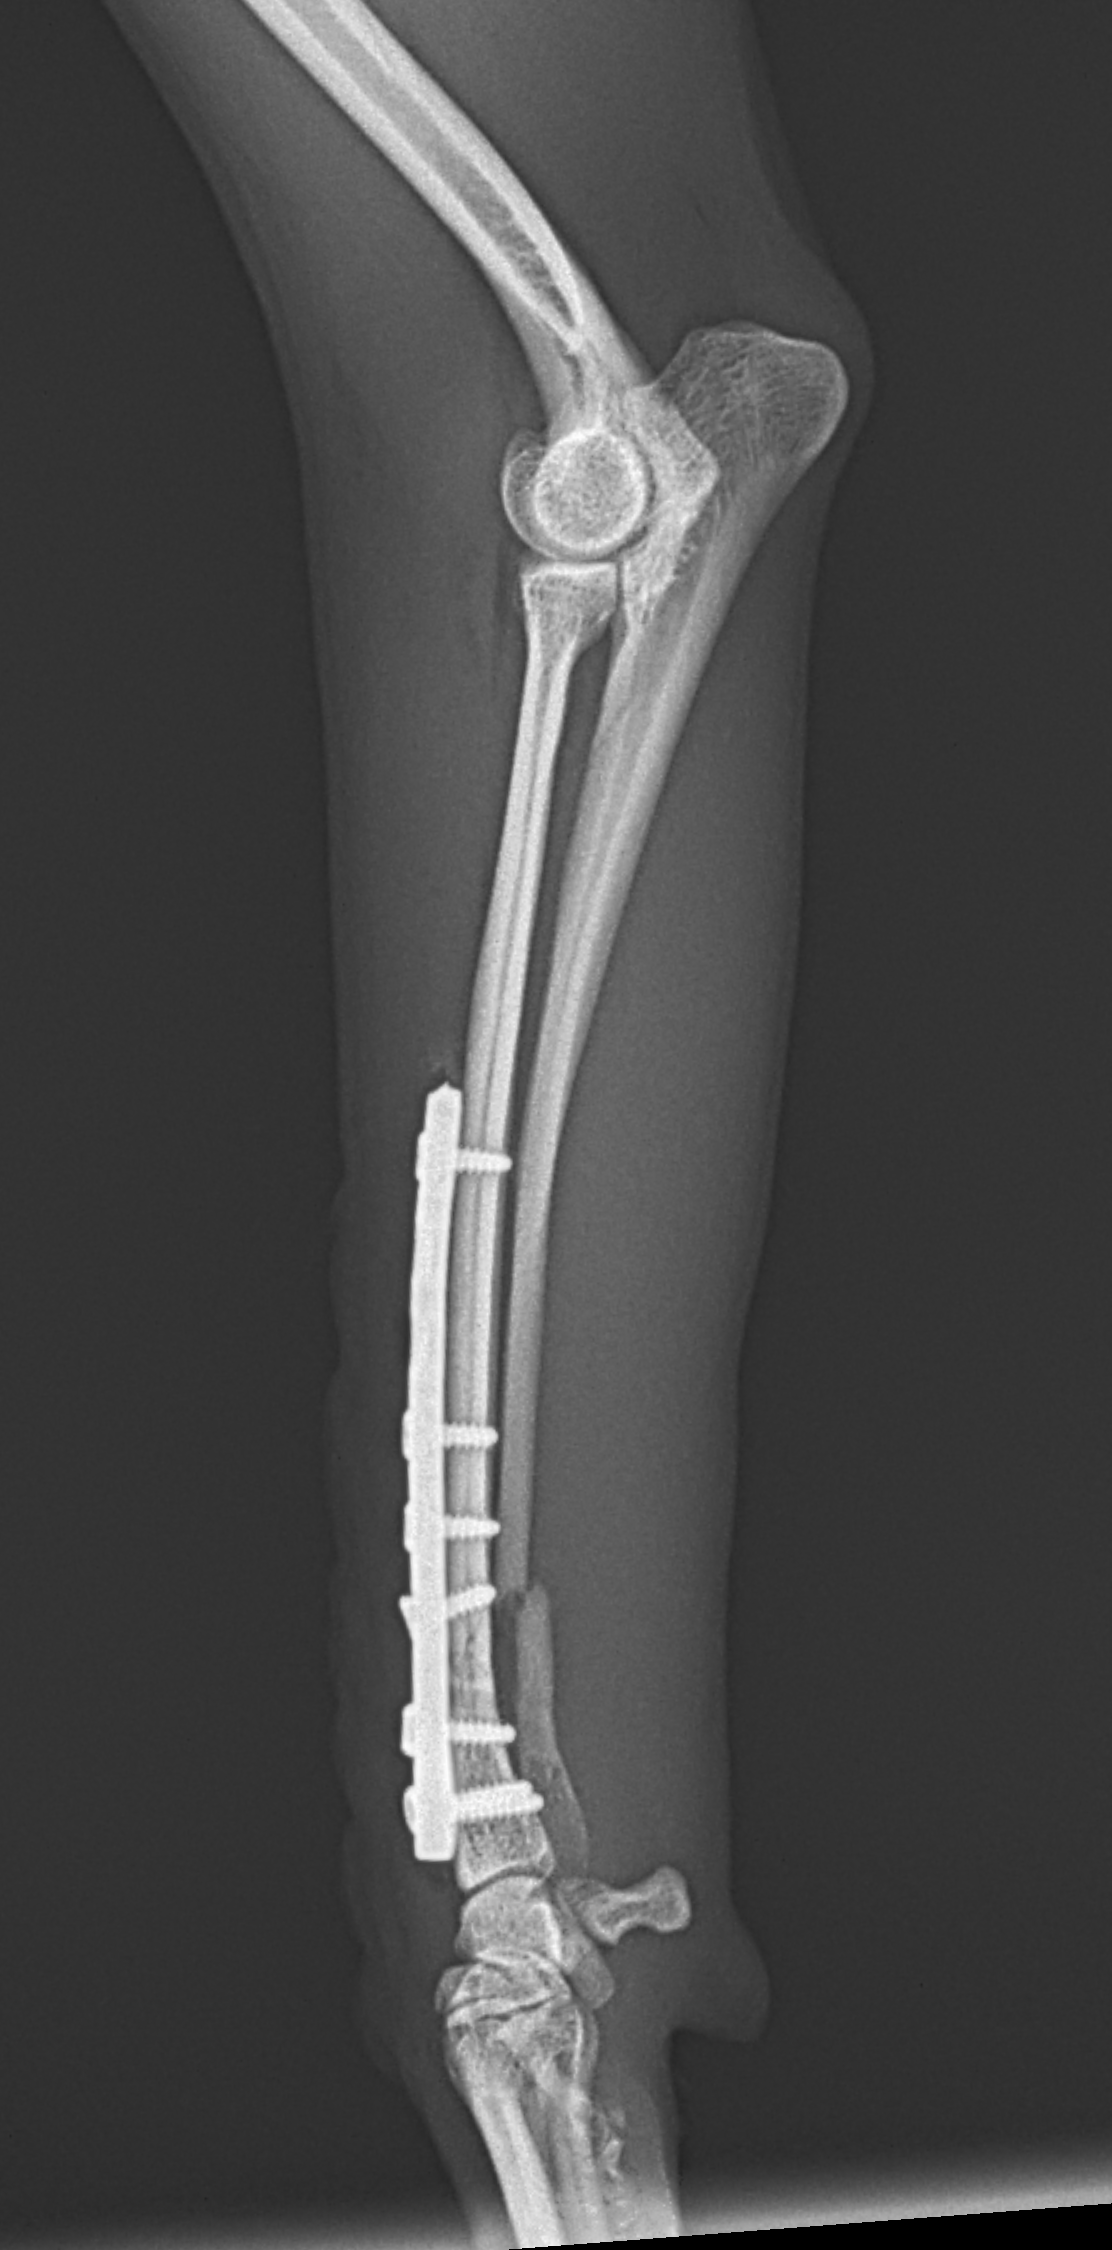

橈骨固定 #264

Toy Poodleさんが室内で転倒して骨折したとのことでかかりつけ医より整復依頼がありました。遠位端骨折です。T style Titanium Plateにコンベンショナルスクリューとロッキングスクリューを組み合わせて骨接合術を行いました。しばらくは安静が必要です。